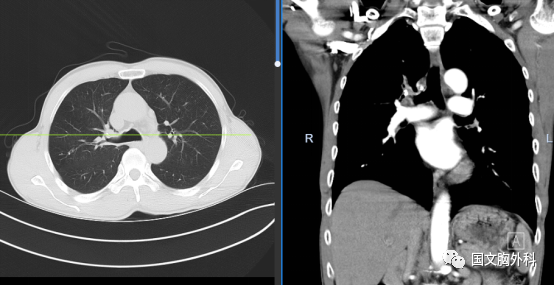

術(shù)中患者右肺門分離困難,決定行右肺上葉袖型切除,在長(zhǎng)達(dá)8小時(shí)的奮斗后,周大爺手術(shù)順利結(jié)束。